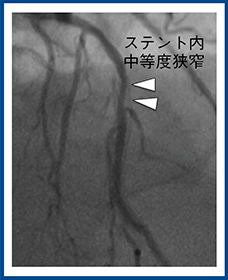

本邦のガイドライン4)では,ステント径が3mm未満の場合,現状のCTでは診断精度が低いため,CTによる評価は推奨していない。当センターで,Aquilion PrecisionとADCTでほぼ同時期に撮影したステント留置症例の画像(図4)を比較すると,ADCTではステント内腔はほとんど評価できないのに対して,Aquilion Precisionでは内腔の狭窄をしっかりと評価できることがわかる。CAGで,ステント近位部に中等度狭窄があることが確認できた(図5)。

空間分解能向上によりブルーミングアーチファクトが軽減したことで,ステント内狭窄の評価が可能になったと考えられる。今後,ステント内狭窄の診断精度や小径ステントの評価能について検証していく必要がある。

図4 ステント留置症例の画像比較(80歳代,男性,労作時胸痛)

13年前にLAD midにステント留置(サイズ不明)

図5 図4の症例のCAG